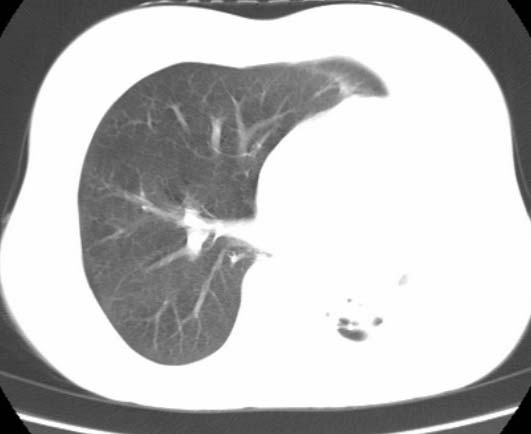

标题: CT25648:求教:是肺发育不全还是结核?

女  20岁。一月前咳血,诊“肺结核”抗痨治疗一月后,咳血停止,现复查。病人精神好。前后ct片对比未见明显变化。既往体检“正常”

1)考虑左肺结核并肺不张、支气管扩张。2)纵隔疝。

以前体检正常只能考虑左肺结核并肺不张、支气管扩张。2)纵隔疝。

考虑左肺结核,左肺毁损,纵膈左偏,既往体检正常不可靠,tb一个月也不会这个样子的,有钙化,应该病程较长,冰冻三尺非一日之寒!

左肺发育不全。

考虑左肺结核,左肺毁损,纵膈左偏,既往体检正常不可靠,tb一个月也不会这个样子的,有钙化,应该病程较长,冰冻三尺非一日之寒

结核,左肺毁损。